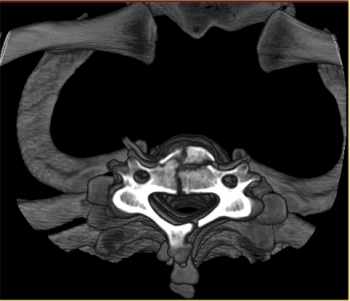

CT Scan/Myelogram

A CT Scan is a simple non-invasive procedure that enables medical professionals to obtain diagnostic information on the brain, chest, abdomen, pelvis, spine and extremities. A myelogram is often performed in the hospital setting where contrast dye is injected into the spinal canal. X-rays are taken and the test can show obstructive lesions in the spine.